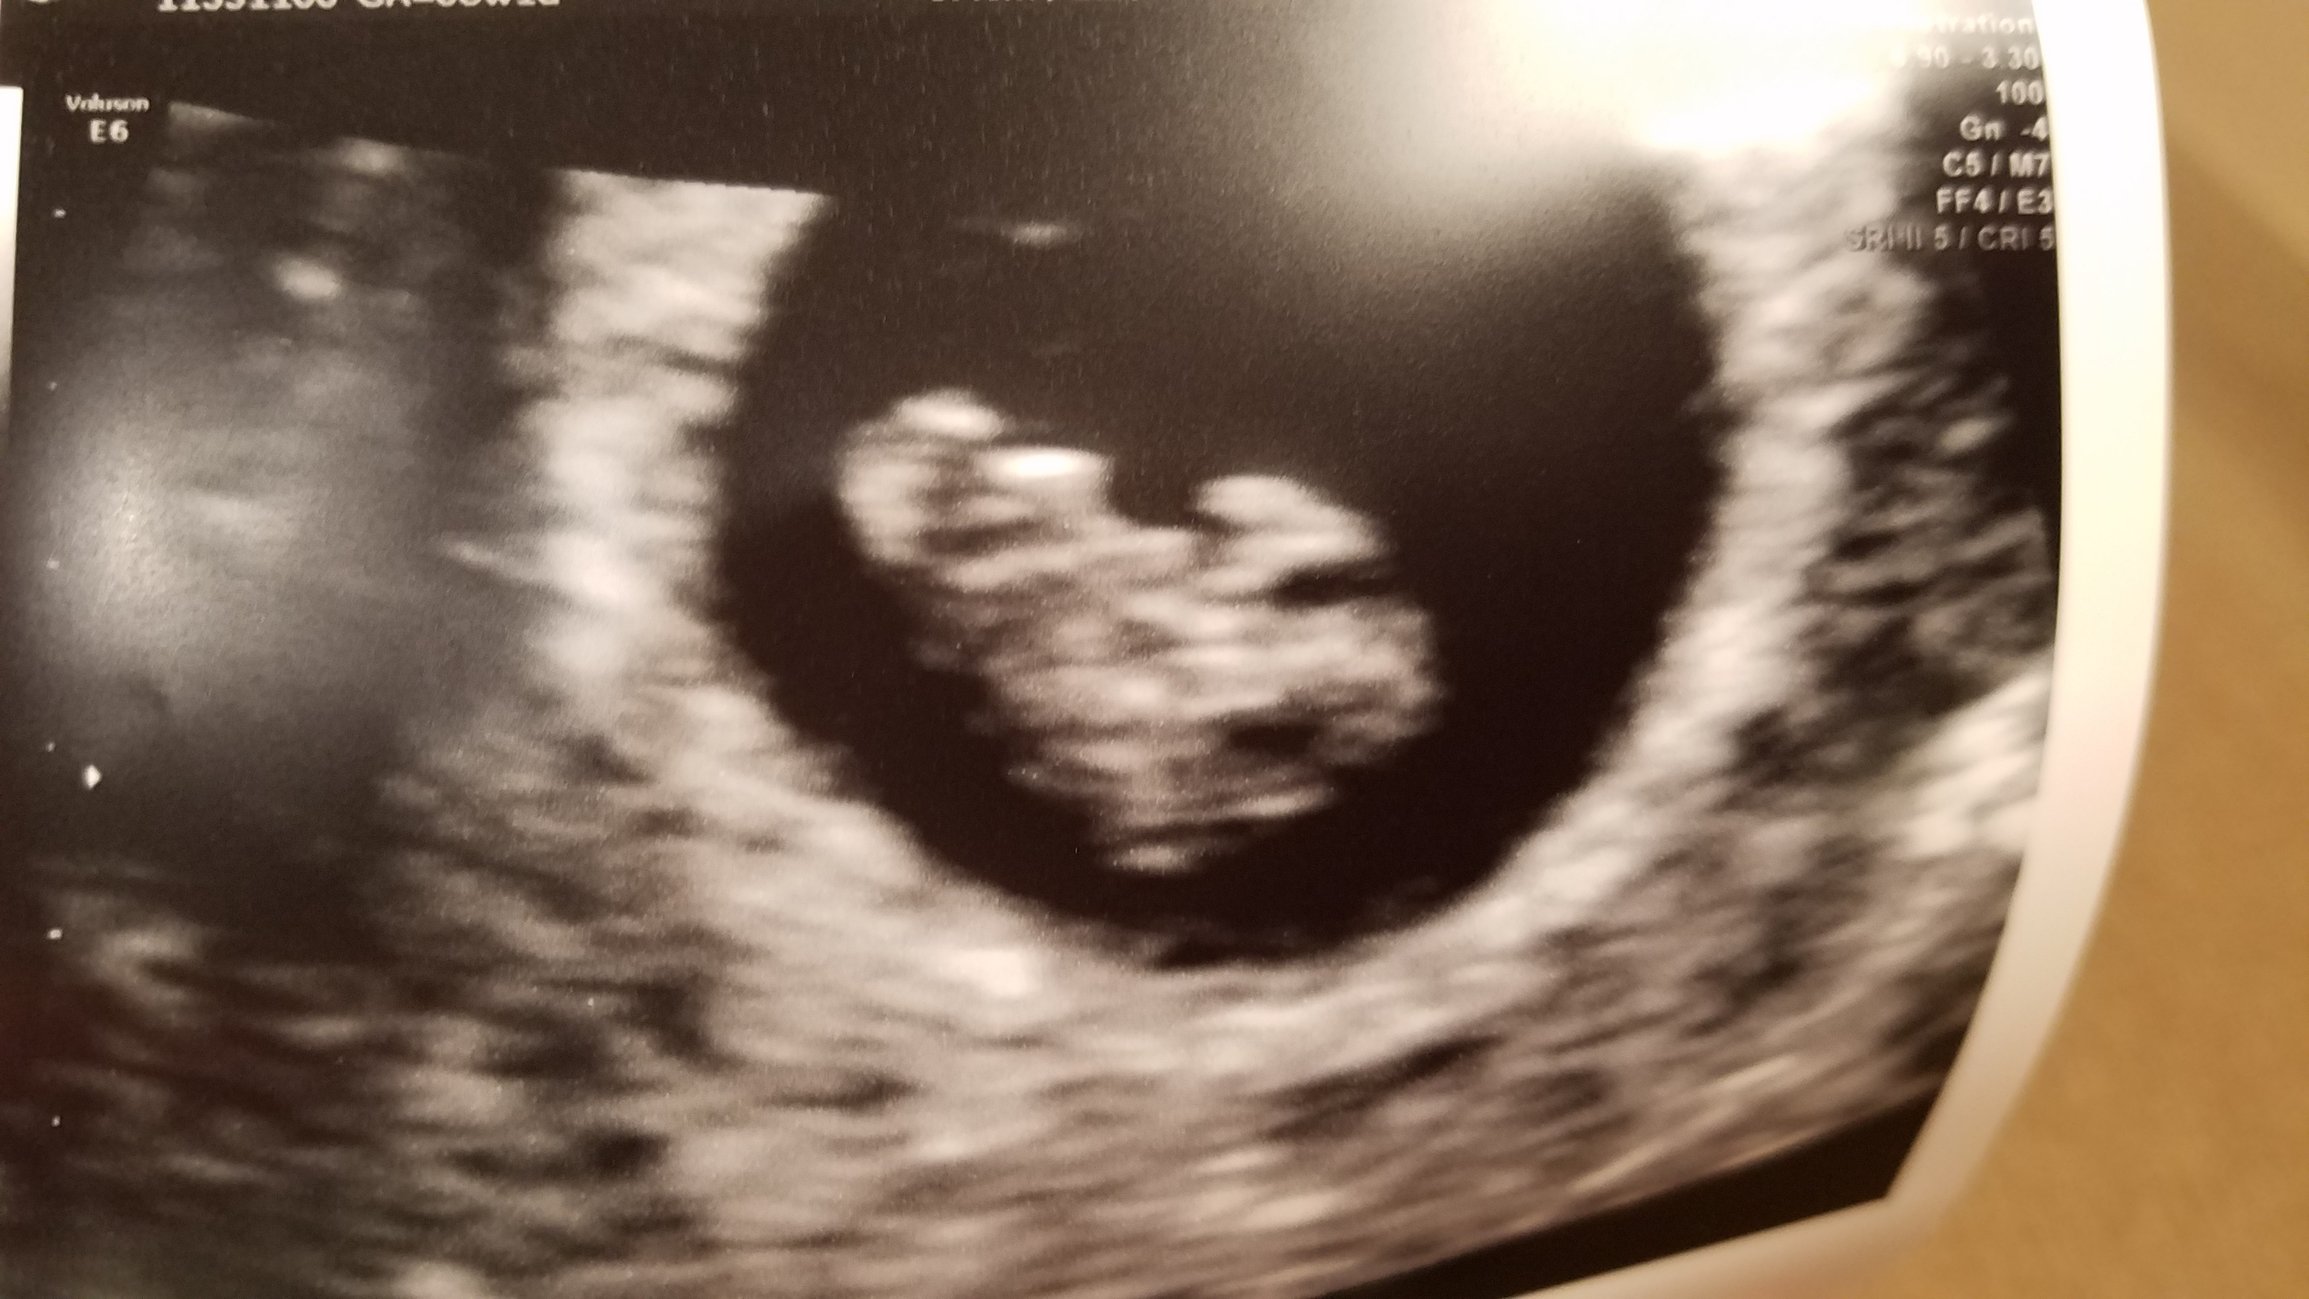

Hi everyone, 6 weeks ultrasound. I’m scheduled back for an 8 weeks ultrasound. Doctor said it’s twins but one is smaller than the other one that we had to wait and see if the other progresses. Has anyone had a similar situation? This is my 3rd pregnancy but first time twins.